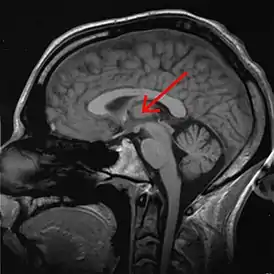

![]() Таламус человека на МРТ-снимке, отмечен стрелкой | |